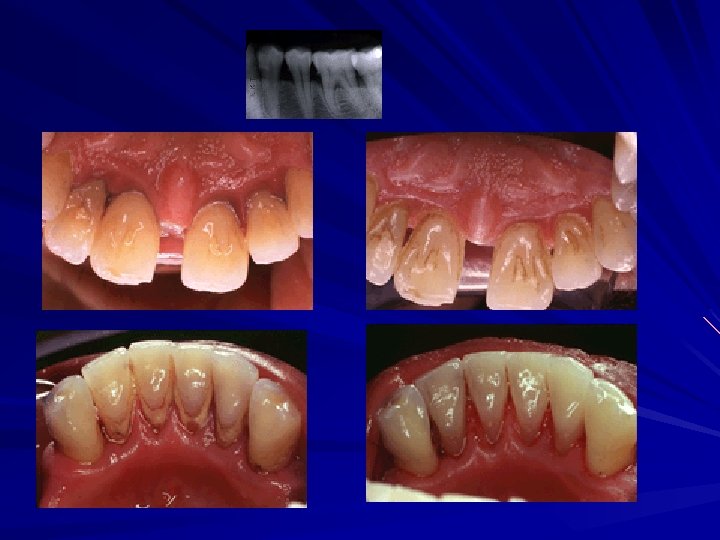

Before Scaling & Root Planing After Scaling & Root planing